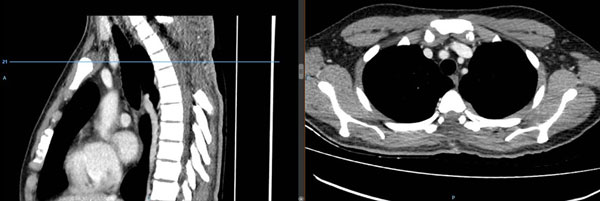

Figura 2. Tomografía computada de columna dorsal con contraste. Se evidencia laminectomía D2 – D6, no se observa lesión hipercaptadora de contraste sugerente de lesión neoproliferativa residual.